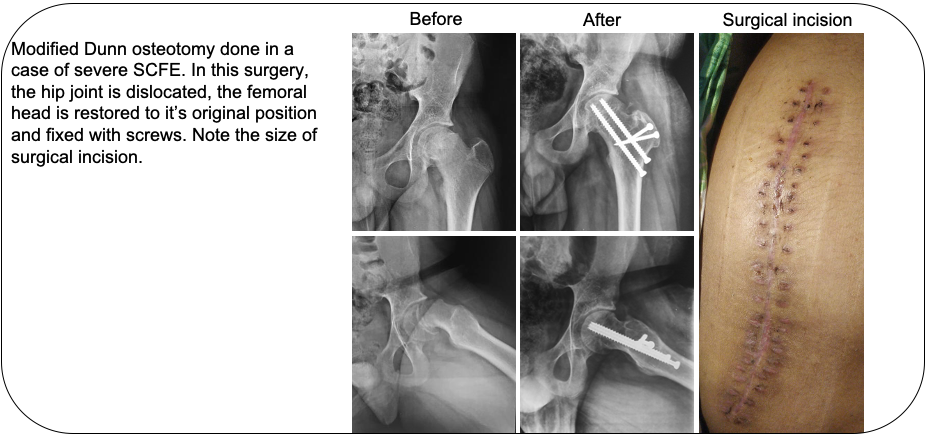

Pediatric Surgery